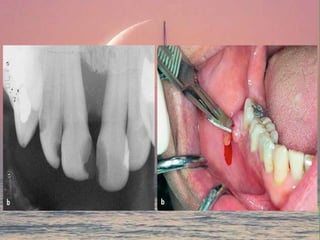

Prior to surgical drainage,

a sterile aspirate is obtained for culture and sensitivity

Palatal abscess , incision parallel to the greater palatine vessels

An incision at submandibular region should be placed two fingers’ breadth

below the lower border to avoid injury of the marginal mandibular branch of the facial

nerve

- to allow the discharge of tissue fluids and pus from the wound by

keeping it patent

- allows for debridement of the abscess cavity by irrigation